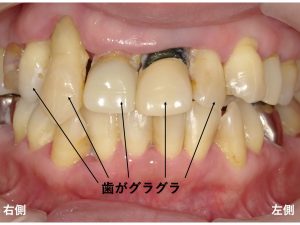

早速口腔内写真から見てみましょう!

以下が初診時です。

かなり審美的に問題がありますよね。

なんとかしないといけません。

この状態では口を大きく開けて笑うことが苦痛になってしまいます。

問題となるのは、

この見た目だけではありませんでした。

歯はグラグラです。

歯周病 と 噛み合わせの問題により

すぐにでも取れそうな状態です。